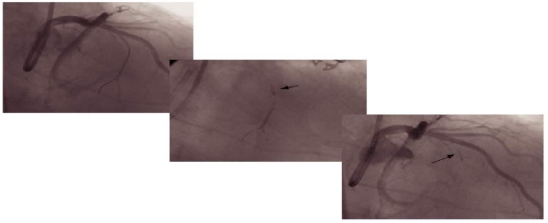

(术前心脏彩超

2020810日,陈玺全副主任带领段青松主治医师在患者局麻,清醒的状态下,顺利完成了手术。手术过程经历近四个小时。术后,患者胸闷、胸痛症状明显好转,未再有晕厥症状出现。复查心脏彩超显示患者左室流出道梗阻症状及二尖瓣反流明显缓解,左心房大小降至正常水平,进一步证实了该手术在肥厚梗阻型心肌病治疗上的有效性。

(术后心脏彩超